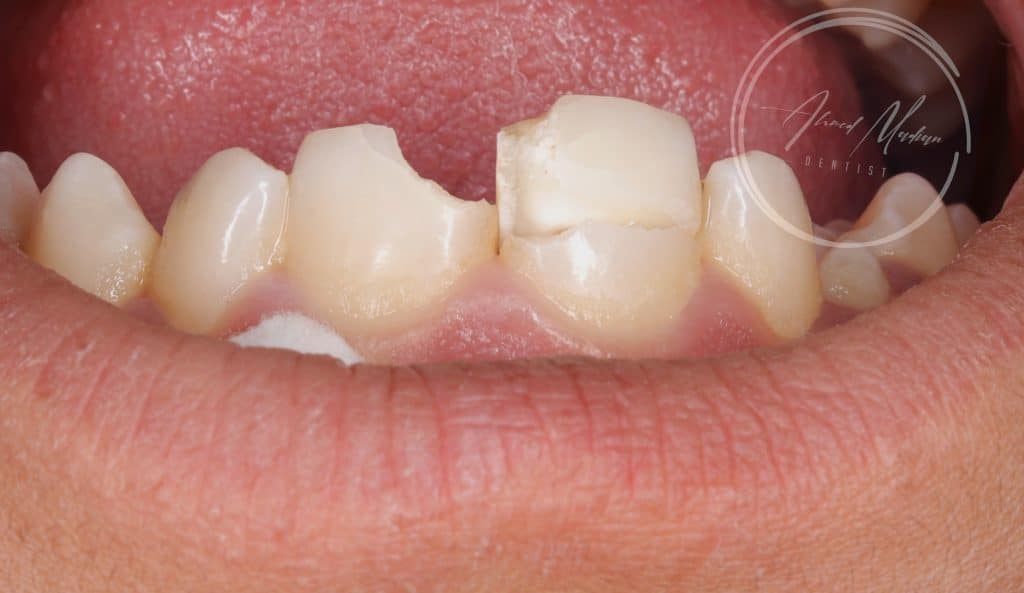

14 y male patient came to the office complaining of trauma in the anterior region

Tooth no 11 showed complicated crown root fracture , exposed pulp , closed apex

Tooth no 12 uncomplicated corwn fracture , class lV

Now patient situation is stabilized and will under go regular follow ups and will be referred to orthodontist for further assessment